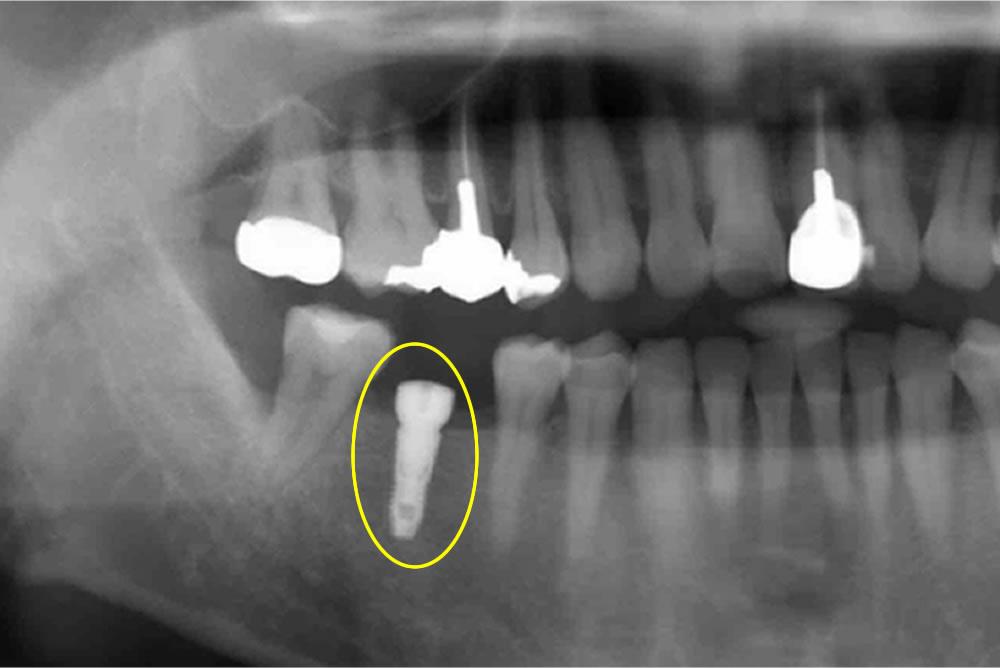

インプラント治療でもっとも大事なポイントは、術前の【診査・診断】です。インプラント治療を行う前に骨の状況はどうか、神経との距離はどのくらいかなどの情報をいかに正確に判断できるかがオペの成功を大きく左右します。

その診査診断に大きく役立つのが歯科用CTです。レントゲンではわからない3次元のスライス画像を元に神経や骨との関係を細かく確認できるようになりました。安全にインプラントを行う為には必要不可欠です。

インプラント治療を新津田沼歯科クリニック奏の杜で行う場合は明らかに難易度の低いインプラントを行う場合をのぞいて、CT撮影を行うようにしています。絶対あってはならないインプラント事故を防止するために。

当院では、“リスクを最小限に抑えたインプラント治療”のために、事前に歯科用C Tを用いた画像診断・シミュレーションを必ず行なっております。